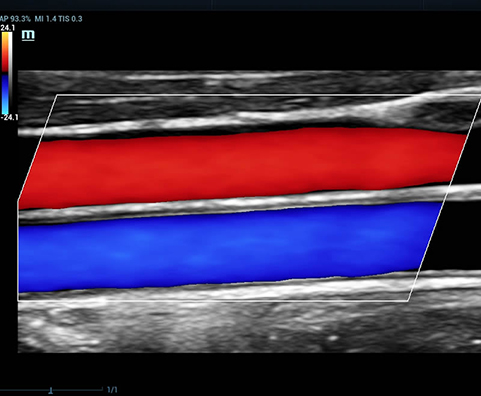

Selain kualitas gambar premium, Resona 7 juga meningkatkan kemampuan penelitian klinis dengan V Flow revolusioner untuk evaluasi hemodinamika vaskular, serta pengambilan penampang tercanggih dari rangkaian data 3D untuk diagnosis CNS pada janin. Kombinasi pengoperasian multisentuh berbasis gerakan yang paling intuitif dengan semua fitur klinis penting membuat Resona 7 menjadi gebrakan baru dalam inovasi ultrasound.